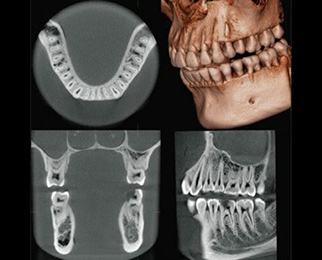

CTとサージカルガイドで、もっと安全に

当院ではすべてのインプラント治療でCTと専用ガイドを使用し、骨の状態や神経の位置を正確に確認したうえで、理想的な位置にブレなくインプラントを埋入します。

見えない部分こそ丁寧に。

安心してお任せいただける治療を心がけています。